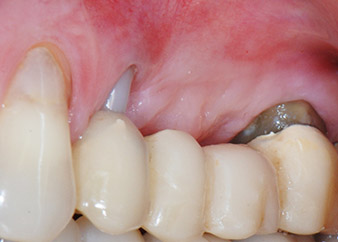

Die Abbildungen 17 und 18 zeigen das klinische Ergebnis zwei Monate nach dem Eingriff. Die nun verminderte Beweglichkeit des Zahns 24 lag bei Miller-Klasse 1 und das Weichgewebe war entzündungsfrei. Um eine neue Infektion zu verhindern und das epitheliale Attachment nicht zu zerstören, wurde auf eine Sondierung zu diesem Zeitpunkt verzichtet. Die nächste Untersuchung sollte bei der Freilegung und dem Verschrauben der Gingivaformer stattfinden, sechs Monate nach dem Einsetzen der Implantate.

Schon bei der Kontrolle zwei Monate nach Implantation hatte sich die Beweglichkeit des verbliebenen „Zahnelements“ 24 von Miller-Klasse 2 zu Klasse 1 verringert. Das weichgewebige Attachment entsprach dem des benachbarten Zahns 23. Die Prognose muss möglicherweise bei der Freilegung angepasst werden, da keine weiteren endodontischen oder parodontalen Symptome vorlagen. Da allerdings fast der gesamte bukkale und approximale Knochen fehlen und der Stumpfaufbau bis zum apikalen Wurzelabschnitt reicht, ist aufgrund biologischer Faktoren kein höheres Attachmentniveau mehr zu erwarten (Sculean et al., 2008).